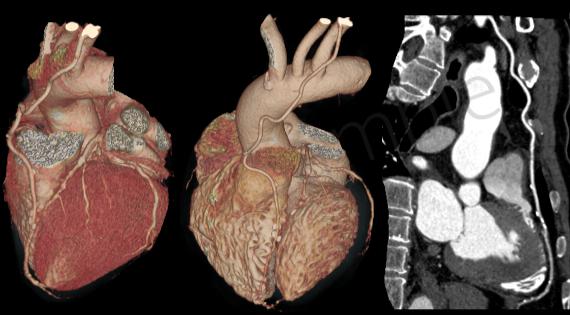

一、心血管疾病的診斷

由于該機(jī)掃描速度快、檢測(cè)范圍廣,使整個(gè)心臟掃描可以控制在5秒內(nèi)完成,實(shí)現(xiàn)了心血管疾病的無(wú)創(chuàng)早期診斷、心功能評(píng)價(jià)及術(shù)后療效評(píng)價(jià)。在冠心病、先天性心臟病、心瓣膜病、心臟腫瘤的診斷發(fā)揮重要作用。

三、CT血管成像

CT血管造影(CTA,CT angiography)具有無(wú)創(chuàng)和操作簡(jiǎn)便的特點(diǎn),對(duì)于心臟、頭頸部、胸腹部甚至四肢的血管變異、血管疾病、血管狹窄、動(dòng)脈瘤、主動(dòng)脈夾層以及顯示病變和血管關(guān)系有重要價(jià)值。